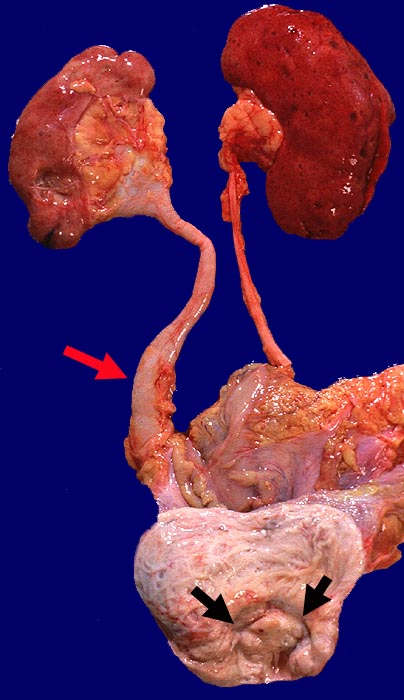

Prostatakarzinom: Tumorinfiltration von Harnblase und rechtem Ureter

Hydroureter rechts. Tumorinfiltration im Bereich des Trigonums.

Metastasierendes Adenokarzinom der Prostata. Hydronephrose rechts.